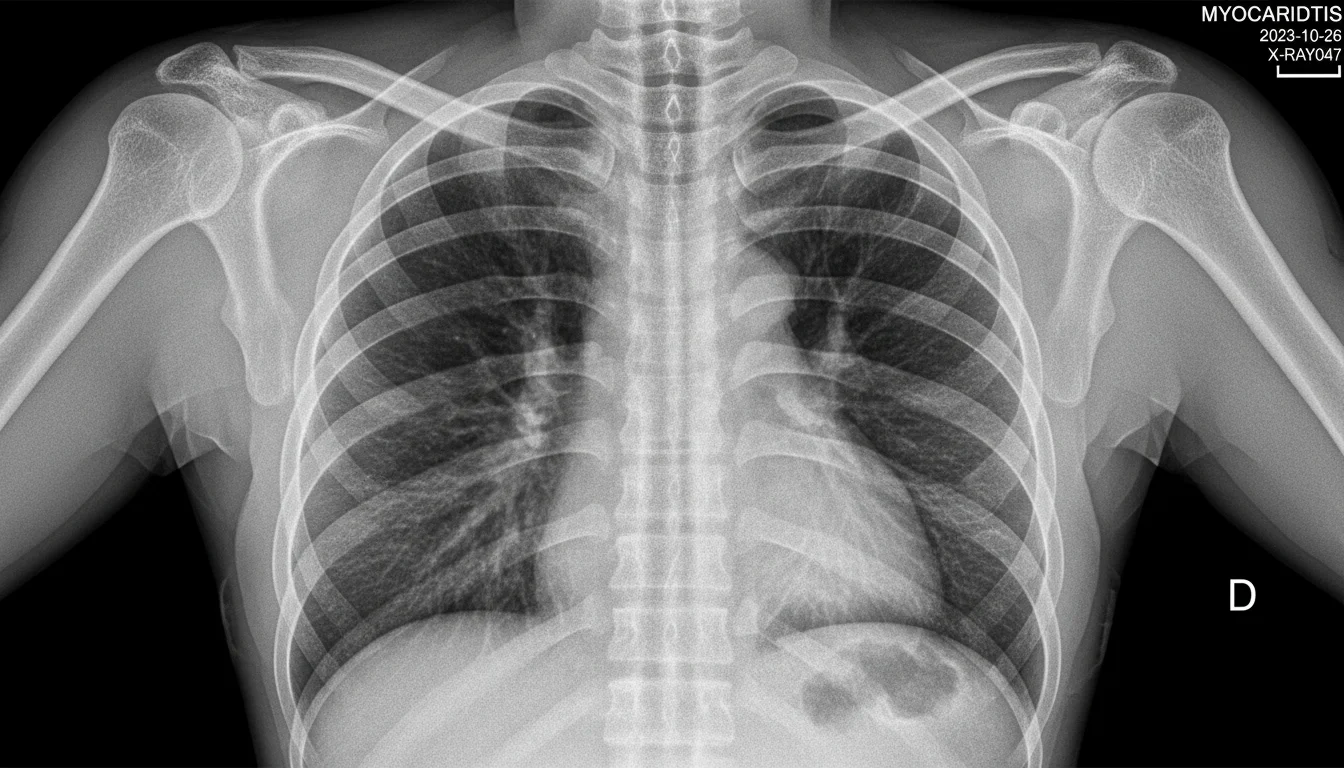

Vier Jahre lang wurde jeder, der Herzmuskelentzündungen nach Covid-19-Impfungen ansprach, als Verschwörungstheoretiker abgestempelt. Jetzt räumen selbst Regulierungsbehörden wie die FDA ein, was Kritiker von Anfang an sagten – und die Studienlage ist verheerender, als das offizielle Narrativ je zugeben wollte, wie das Aktionsbündnis freie Schweiz (ABF Schweiz) in einem aktuellen Bericht dokumentiert.

Das Schweizer Aktionsbündnis hat vier hartnäckige Mythen rund um impfbedingte Myokarditis unter die Lupe genommen – und kommt zu einem vernichtenden Befund: Alle vier sind durch aktuelle Forschung widerlegt. Was bleibt, ist der bittere Nachgeschmack einer globalen Impfkampagne, bei der das Nebenwirkungsprofil nach Eingeständnis der RKI-Protokolle bewusst erst „post marketing“ erhoben werden sollte. Ein laufender Menschenversuch, protokolliert, gewusst, durchgeführt.